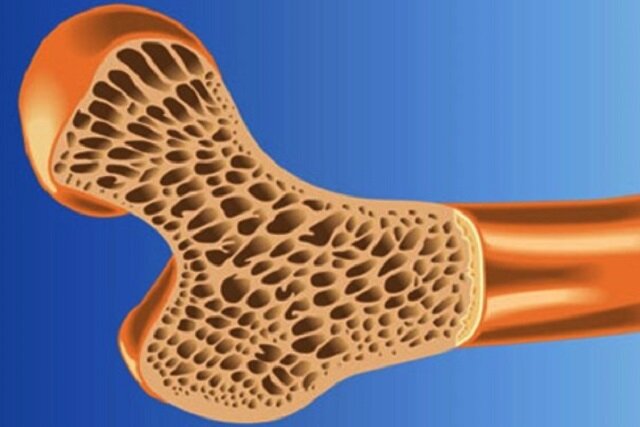

شکستگی، تنها نشانه پوکی استخوان است

مدیر کلینیک طب پیشگیری و ارتقای سلامت سازمان جهاد دانشگاهی علوم پزشکی تهران با بیان اینکه شکستگی تنها نشانه پوکی…

برای سلامت استخوان چه چیزی بخوریم؟

آفتاب نیوز : روزی کریر متخصص تغذیه از برنامه تغذیه سالم Second Nature می گوید: “ویتامین D برای سلامت استخوان…